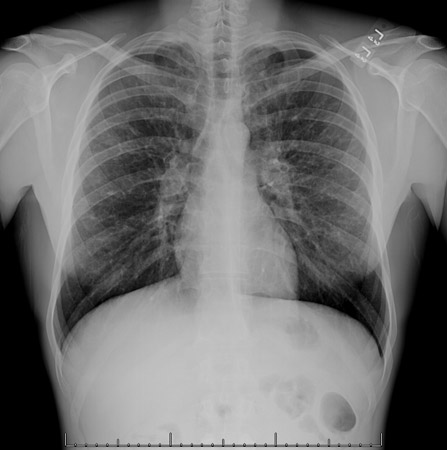

Radiografía de tórax que muestra una adenopatía hiliar bilateral en un paciente con sarcoidosis

De la colección personal del Dr. M.P. Muthiah, Departamento de Medicina Intensiva y Pulmonar y Medicina del Sueño, University of Tennessee